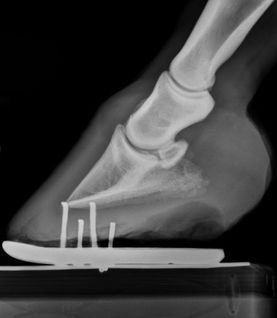

Digital radiography is used to view images of bone and soft tissue. The images are digital, rather than film and are available immediately, allowing for quick, on-site assessment of problems. The ability to manipulate the images on the computer and enhance specific regions of the image allows for better visualization of the problem areas.

Radiography is most commonly used in horses to view problems within the legs, making it an invaluable tool for lameness evaluations. Radiography is also very helpful in pre-purchase examinations, by helping uncover underlying or potential lameness issues before they manifest themselves symptomatically.